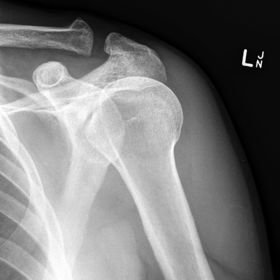

| Grashey | Insufficient obliquity |

| Grashey | Excessive obliquity |

| Grashey | MCP is tilted posteriorly |

| Scapular Y-Lateral | ANATOMY: humeral head resting in the 'Y' of the acromion and coracoid process CRITERIA: vertebral border and lateral border of scapula are directly superimposed humeral head is aligned with body of scapula POSITIONING: pt's unaffected arm is abducted 90 degrees, pt in 45-60 degree anterior oblique CR perpendicular @ scapulohumeral joint (neer) CR angled 10-15 degrees caudal @ scapulohumeral joint |

| Inferosuperior Axial Shoulder | ANATOMY: lateral view of the proximal humerus in relation to the glenoid fossa CRITERIA: lesser tubercle in profile medially humeral head is in the center of VOI POSITIONING: affected arm abducted 90 degrees, hand rotated externally with hand supinated CR horizontal 25-30 degrees medial to the scapulohumeral joint |

| Posterior Oblique Grashey | ANATOMY: glenoid cavity in profile glenohumeral joint center of VOI CRITERIA: open glenoid cavity anterior/posterior rims of glenoid cavity are superimposed POSITIONING: pt in 35-40 degree posterior oblique CR perpendicular @ glenoid cavity |